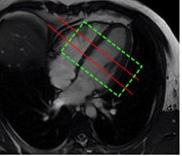

Planification des séquences

La séquence d’OS a été établie, et on peut voir ce qui se passe au cours des différentes phases des manœuvres respiratoires. L’étape suivante consiste à planifier cette séquence, ce qui est très simple. La première coupe est une coupe mi-basale qui est stratégiquement placée pour éviter la voie d’éjection du ventricule gauche (LVOT), et les valves atrio-ventriculaires. La deuxième est une coupe mi-ventriculaire. On vérifie le cycle cardiaque pour s’assurer du bon positionnement. Notez 3T GE

comment le shim est concentré autour des deux coupes et non du cœur complet ! (figure 2.)

A B C

Figure 2 : Images montrant les positions correctes des coupes mi-basale et mi-ventriculaire et le bon placement du shim. A- Aspect 4 chambres, B- Aspect 2 chambres et C- Coupe axiale.